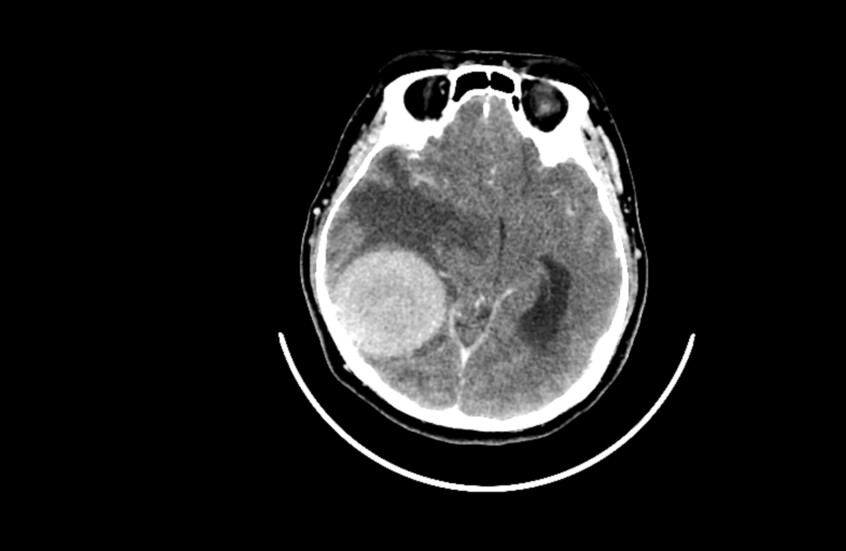

• اكتشاف سبب التهاب القلب النادر بعد لقاحات "كوفيد_19"